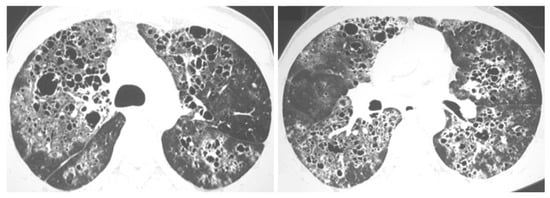

2.3. Chronic Cavitating Disease

2.4. Disseminated Infection